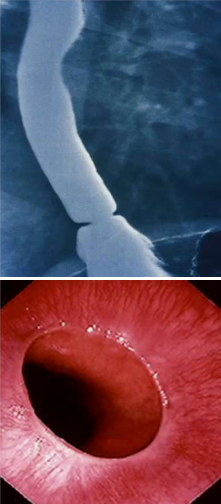

Schatzki rings occur near the GE junction and respond well to esophageal dilation.

How do you confirm this diagnosis?

This is eosinophilic esophagitis, note the eosinophilic microabscesses on the esophageal wall and concentric rings. This is diagnosed by biopsy w/15-20 Eos per high power field.

How do patients with EoE typically present first and how do you first manage them?

1st: intermittent dysphagia. Treat w/PPI, then if that doesn’t work you treat with topical steroids.

How do you diagnose and treat this patient?

This patient has an esophageal web, which responds extremely well to esophageal dilation.

What type of dysphagia will this patient present with?

Progressive solid food dysphagia. This is a peptic stricture from long standing GERD that has damaged the mucosal lining of the esophagus.